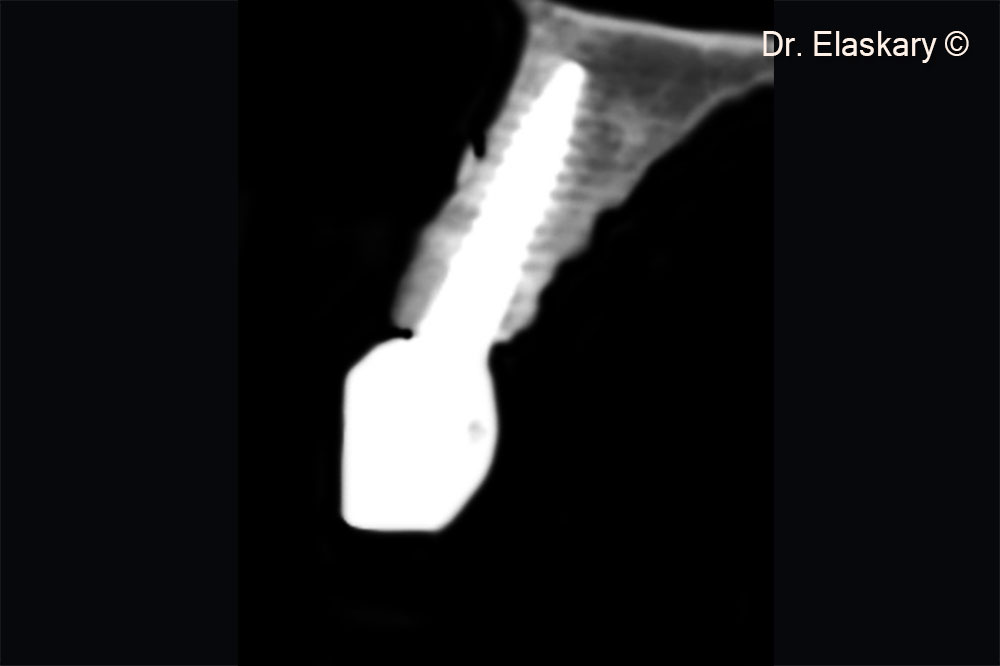

CBCT scan showing a sagittal section of broken central incisor , with lost labial plate of bone